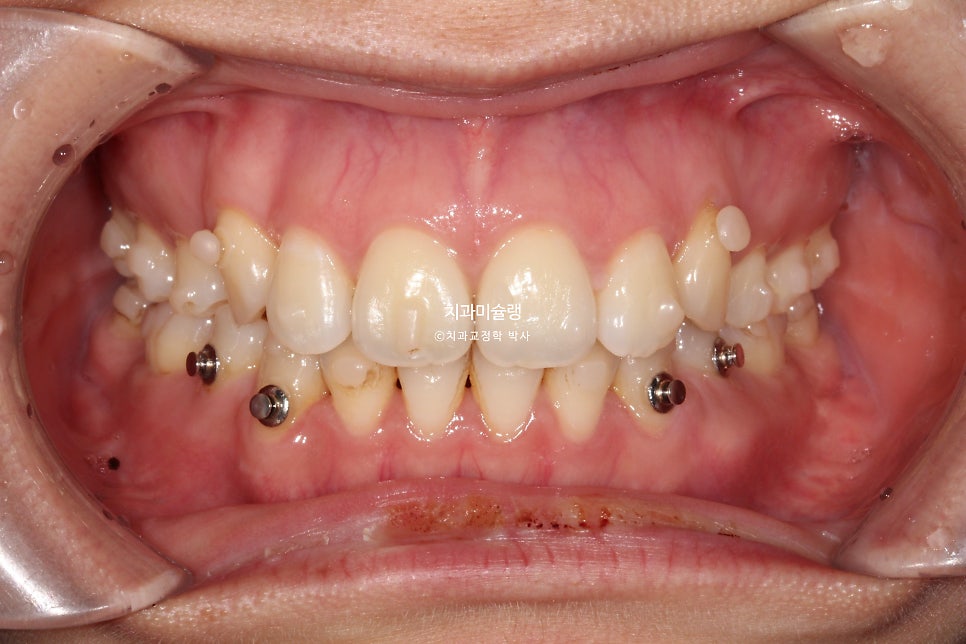

중심선은 잘 맞으며 송곳니는 제자리로 잘 내려왔죠. 개방교합도 완벽히 개선되었습니다.

어금니 교합은 이미 좋습니다.

두 번째 재제작

약간의 교합 개선과 발치공간이 미세하게 남아 두번째 재제작에 들어갔습니다.